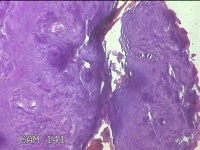

左腕掌侧结节

性别

男

年龄

57岁

临床诊断

皮下结节

一般病史

近3个月来,发现左腕掌侧一结节,无明显疼痛及不适。

标本名称

大体所见

灰白暗红色皮肤样结节1.5x0.8x0.3cm一个,表面糜烂,切面灰白暗红色,质软。

图2